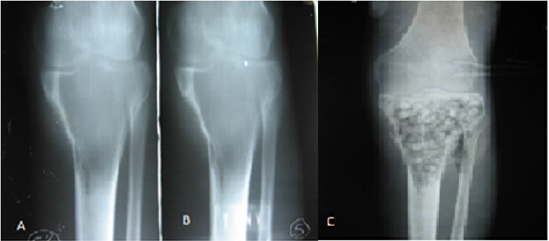

Figure 1:

A. A and B shows the osteolytic epiphysometaphyseal lesion with thinning of the cortices.

B. C Image showing the filling of the lesion with cancellous bone after curettage in the proximal 1/3 of the tibia.